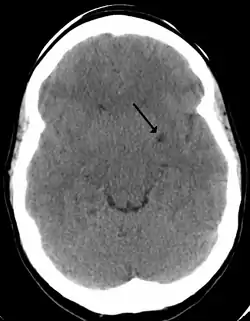

In humans, perivascular spaces surround arteries and veins can usually be seen as areas of dilatation on MRI images. While many normal brains will show a few dilated spaces, an increase in these spaces may correlate with the incidence of several neurodegenerative diseases, making the spaces a topic of research.[4]

Perivascular spaces may be enlarged to a diameter of five millimeters in healthy humans and do not imply disease. When enlarged, they can disrupt the function of the brain regions into which they project.[5] Dilation can occur on one or both sides of the brain.[7]

Perivascular spaces are most commonly located in the basal ganglia and white matter of the cerebrum, and along the optic tract.[13] The ideal method used to visualize perivascular spaces is T2-weighted MRI. The MR images of other neurological disorders can be similar to those of the dilated spaces. These disorders are:[7]

Perivascular spaces are distinguished on an MRI by several key features. The spaces appear as distinct round or oval entities with a signal intensity visually equivalent to that of cerebrospinal fluid in the subarachnoid space.[7][14][15] In addition, a perivascular space has no mass effect and is located along the blood vessel around which it forms.[14]

The clinical significance of perivascular spaces comes primarily from their tendency to dilate. The importance of dilation is hypothesized to be based on changes in shape rather than size.[13] Enlarged spaces have been observed most commonly in the basal ganglia, specifically on the lenticulostriate arteries. They have also been observed along the paramedial mesencephalothalamic artery and the substantia nigra in the mesencephalon, the brain region below the insula, the dentate nucleus in the cerebellum, and the corpus callosum, as well as the brain region directly above it, the cingulate gyrus.[5] Upon the clinical application of MRI, it was shown in several studies that perivascular space dilation and lacunar strokes are the most commonly observed histological correlates of signaling abnormalities.[13]